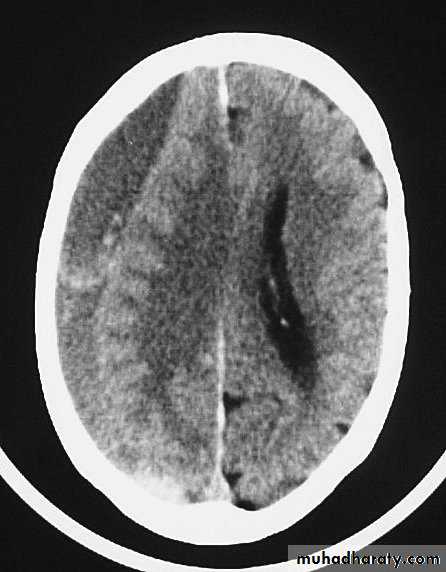

c. Intracerebral Haematoma

This is the least common of traumatic haematoma.

They are due to areas of traumatic contusion coalescing into a contusional haematoma.

Disrupted cerebral tissue release thromboplastins that potentiate haemorrhage.

CT scan: appear as hyperdence lesions with associated mass effect and midline shift.

Large intracerebral haematomas should be evacuated unless the patient’s neurological state is improving.

Small inracerebral haematomas may not require removal, but be aware that they can expand.